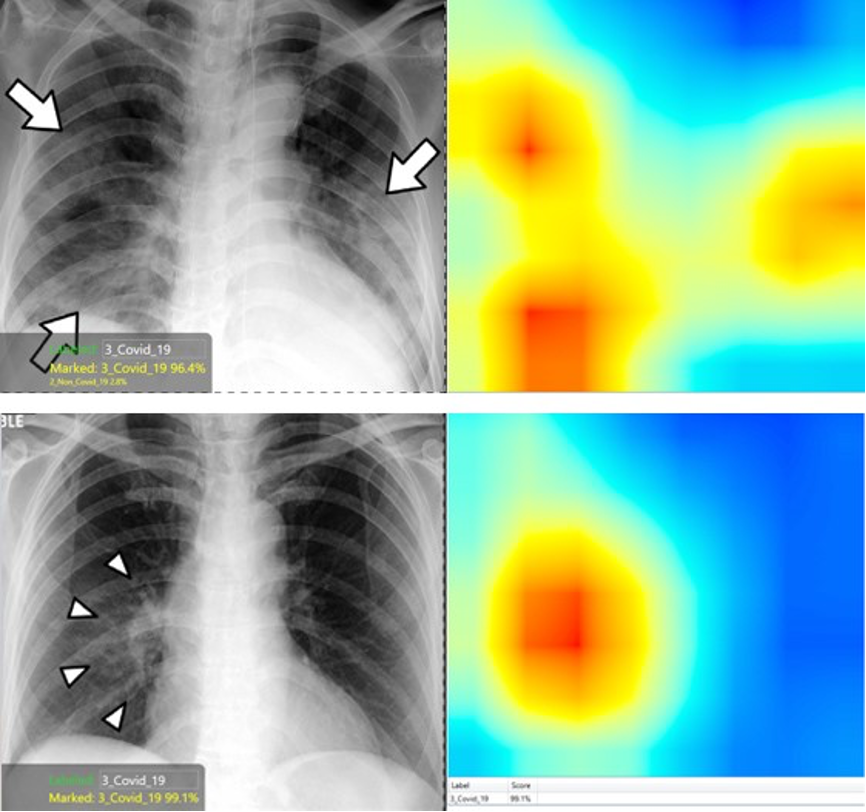

在這種背景下,康耐視VisionPro Deep Learning軟件提供了有用的熱圖功能,其突出顯示了圖像中對于分類非常重要的區域。黃色到紅色區域很重要,而綠色到藍色區域對于決策算法并不重要。

在現實世界中,這種熱圖功能使該工具不僅可以為潛在的診斷提供建議(即Covid-19陽性或陰性),還可以識別出檢測到相應疾病癥狀的區域。這一點很重要,因為它可以幫助放射科醫師在圖像的特定區域進行歸零校正,以使他們能夠驗證或推翻AI診斷,從而防止該軟件工具因錯誤的原因無法做出正確的決策。